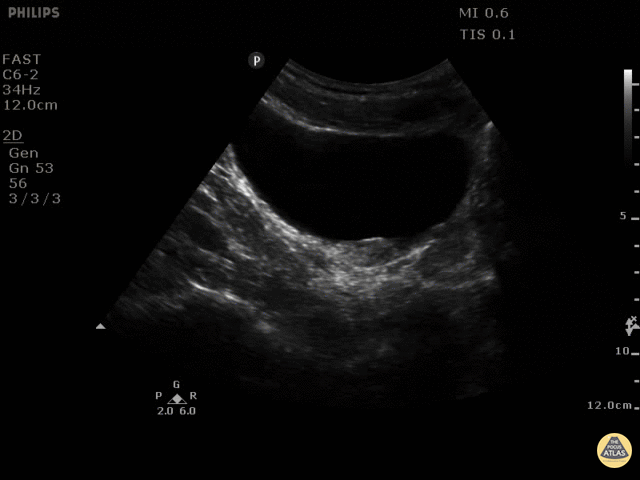

This is a 58 year old man that presented with first episode of severe LLQ pain and vomiting. The differentials were diverticulitis vs nephro/urolithiasis. POCUS was performed obtaining images of left and right kidneys, bladder and aorta. The image shows a 7mm stone seen with shadowing at the L UVJ. Maria Perez; Emergency Registrar; St Vincent’s Hospital; Melbourne - Australia